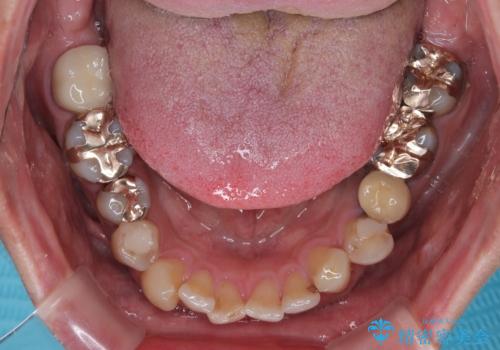

元来むし歯が多く、さらに受け口傾向の咬み合わせを気にしていらっしゃいました。

当初はむし歯処置が必要な歯のみの治療予定でしたが、捻転や咬み合わせを可及的に改善したいとのことで、全顎的にオールセラミッククラウンにて補綴治療を行うこととしました。

反対咬合を補綴治療で改善すると、上唇へ歯が当たる感覚や、発音時の舌感覚が急激に大きく変化するため、違和感になれるまで時間を要することになります。

仮歯で過ごす期間を一定期間も受けることで徐々に変化になれていくようにし、オールセラミッククラウン装着時には違和感なく過ごすことができるようにしています。